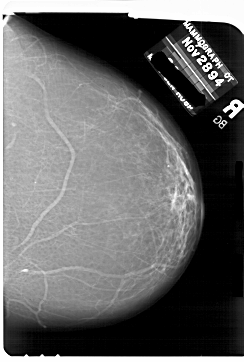

A_1769_1.LEFT_CC

LEFT_CC LINES 6871 PIXELS_PER_LINE 4951 BITS_PER_PIXEL 12 RESOLUTION 43.5 OVERLAY

FILE: A_1769_1.LEFT_CC.OVERLAY

TOTAL_ABNORMALITIES 1

ABNORMALITY 1

LESION_TYPE MASS SHAPE LOBULATED MARGINS ILL_DEFINED

ASSESSMENT 4

SUBTLETY 4

PATHOLOGY BENIGN

TOTAL_OUTLINES 1

BOUNDARY